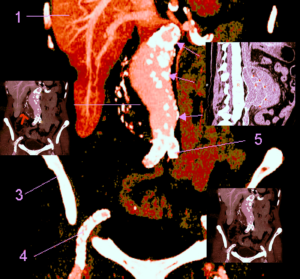

Les mesures effectuées sur un anévrisme doivent inclure le diamètre total incluant le thrombus (flèche bleue) et la lumière. Les images suivantes montrent un anévrisme majeur de 8cm partiellement thrombosé. Il est possible d’utiliser le doppler couleur dans ces circonstances, ce qui permettra d’objectiver l’absence de flux au niveau de la thrombose. L’examen sera complété par une coupe sagittale afin de préciser l’étendue de l’anévrisme (seconde image).

L’angioscanner aorto-iliaque est plus invasif mais plus reproductible que l’échographie et moins opérateur dépendant. C’est l’examen de choix avant un traitement par endoprothèse ou par chirurgie classique. Il permet les mesures exactes (« sizing ») de l’anatomie de l’anévrysme, de l’aorte et des artères iliaques avant mise en place d’une endoprothèse. Il permet la recherche d’autres anévrysmes au niveau fémoro-poplités et d’étudier l’ensemble de l’aorte.